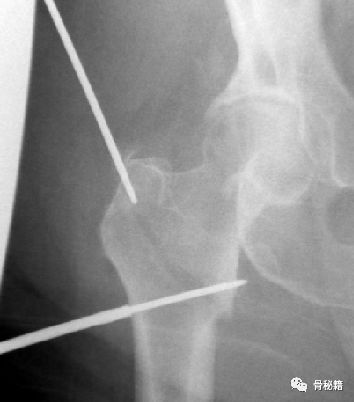

这样一个粗隆间骨折,骨折线经过入钉点,这个时候复位比较困难,及时复位,进钉的时候也很容易将骨折线撑开而造成复位不良。

1.应用螺纹导针,植入到偏前方的皮质 直达内侧的骨折块